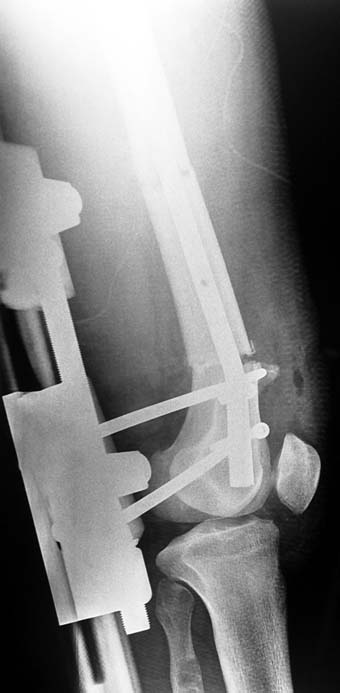

3. POSTTRAUMATIC LOWER LIMB SHORTNESS (MALUNION)

This type of shortness occurs after a fracture heals in a shortened position. Most cases are seen in adults and can be treated with one lengthening operation. Additional deformities can be corrected simultaneously. Most of these cases can be treated with lengthening over nail or just corrections and intramedullary nailing.